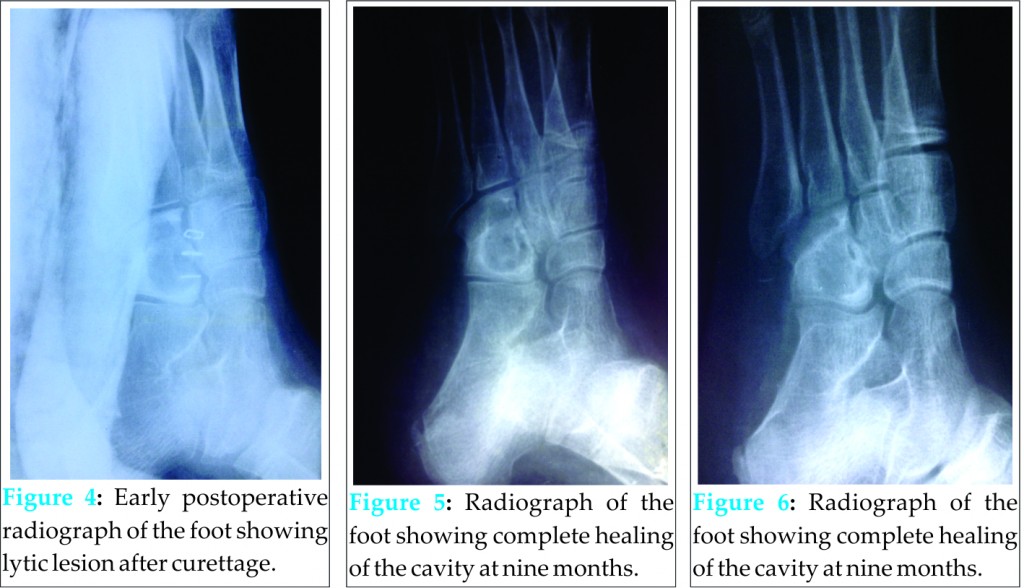

It was curetted till the appearance of punctate bleeding and the wound was closed over Penrose-type drain. Pus culture isolated S. pyogenes, and the dark tissue, on histological examination, revealed dense acute inflammation with foamy histiocytes and fragments of viable bone suggestive of an abscess. On follow-up, he showed complete resolution of disease without recurrence and complete radiological healing was achieved at 9 months (Figs. 3-6).